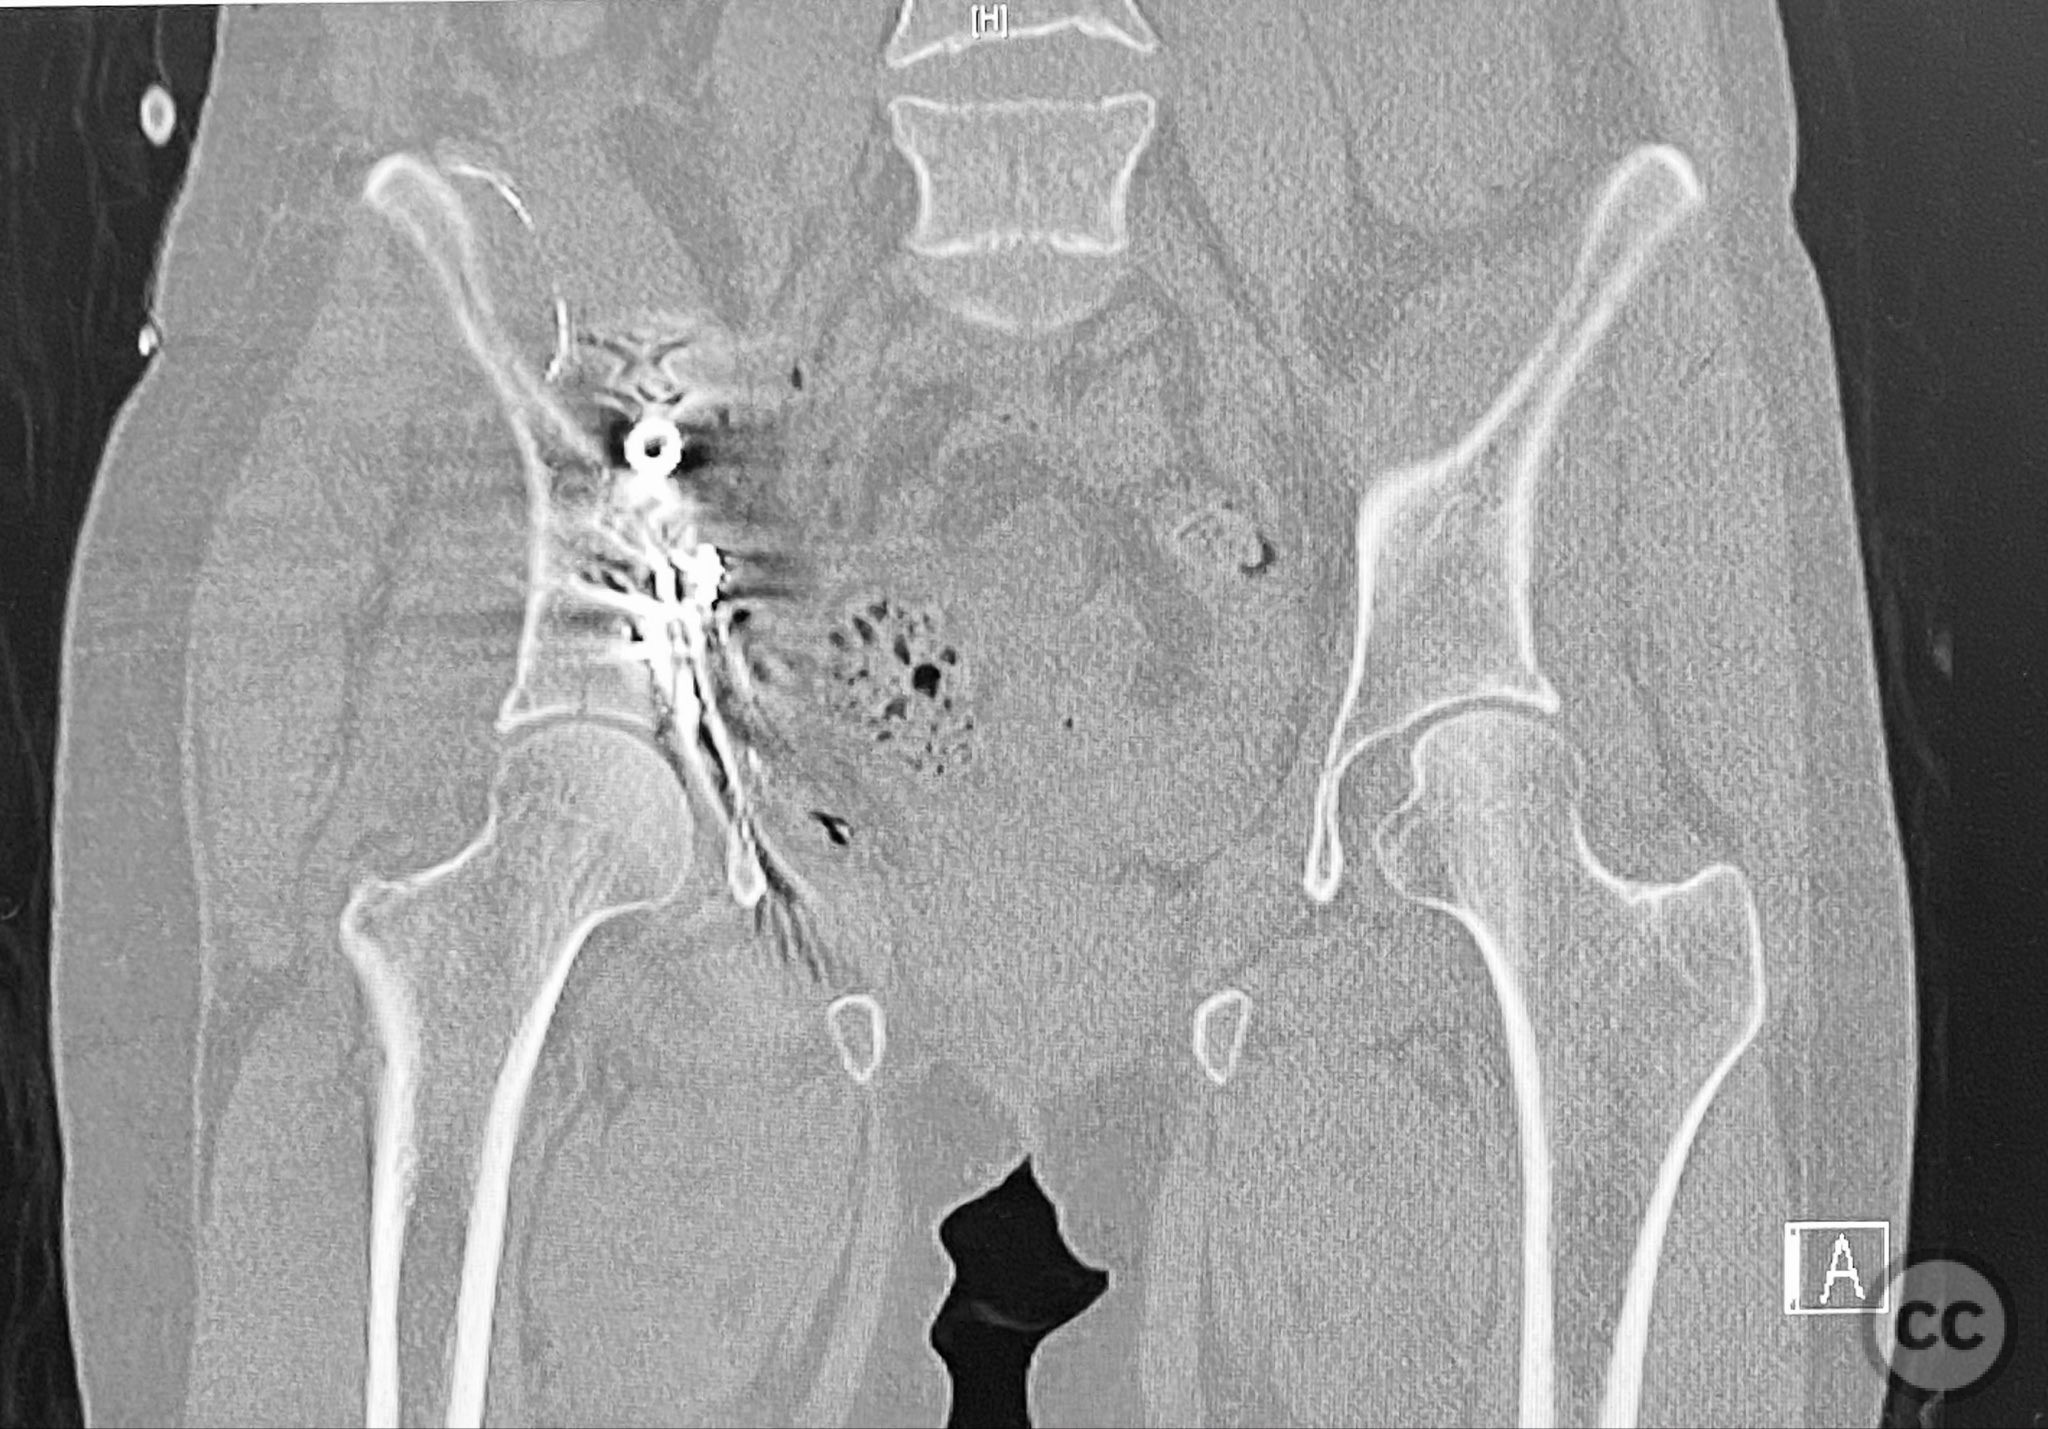

Clinical and radiological findings:  The patient sustained an acetabular fracture with a rare posterior medial dome impaction fragment, as demonstrated on AP pelvic radiographs obtained in skeletal traction. Surface renderings and axial CT images revealed multiple incomplete fracture lines, including a rhomboid-shaped cortical fragment adjacent and proximal to the anterior column/wall fragment. Coronal and sagittal reconstructions further delineated the impacted articular fragment and its relationship to the surrounding acetabular dome. The fracture pattern is classified as AO/OTA 62B3 (associated both-column fracture with dome impaction).

Planning remarks:  The preoperative plan involved an ilioinguinal approach to the acetabulum, utilizing the intrapelvic interval for initial reduction and stabilization of the posterior column with a contoured intrapelvic plate. Sequential reduction of the anterior column and direct management of the impacted dome fragment were planned, facilitated by temporary removal of the rhomboid cortical fragment.

Anatomical surgical approach:  A classical ilioinguinal approach was performed, developing the lateral, middle, and medial windows. The intrapelvic interval was used to access the quadrilateral surface and posterior column. The rhomboid cortical fragment was excised to allow direct visualization and manipulation of the impacted posterior medial dome fragment. Reduction was achieved using a spiked pusher under fluoroscopic guidance. The defect was filled with morselized allograft, and the rhomboid fragment was anatomically reduced. The anterior column was stabilized with a contoured plate. Posterior column reduction was further improved using a reduction clamp applied with one tine lateral to the anterior inferior iliac spine (AIIS) and the other on the quadrilateral surface via the middle window, followed by lag screw fixation.